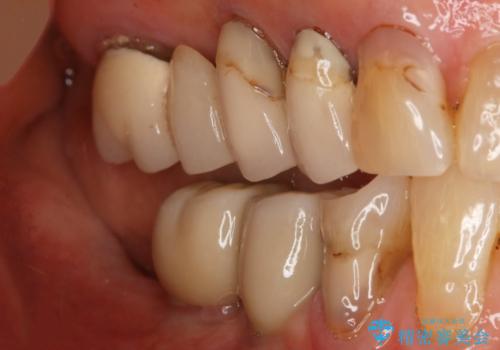

- 数十年前、アメリカで行った治療部位のやり直しを希望されてご来院。

ツギハギの修復が行われてきた被せ物は、縁が合っておらず隙間があり見た目も悪くなってしまっていました。

古い被せ物を除去し、中の状態をキレイにしたうえで改めて金属を使用していない被せ物で噛み合わせの回復を行いました。

被せ物の色は噛み合う反対側の被せ物と合わせて作りました。